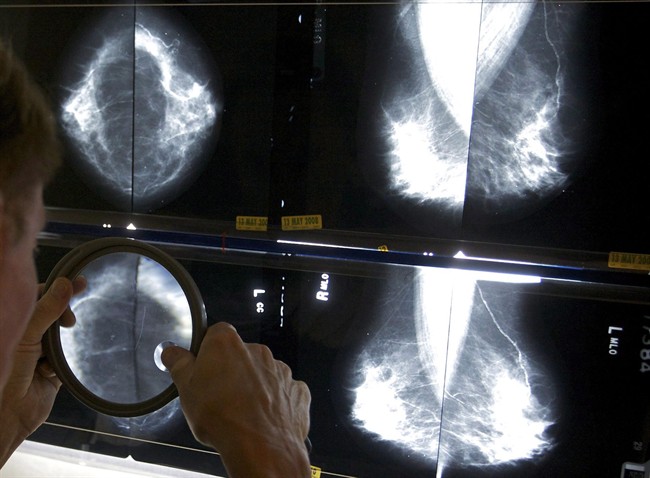

High levels of sugar consumption in the typical Western diet can increase the risk of breast and lung cancer growth and development even after diagnosis, according to a new U.S. study.

A team of researchers at the University of Texas MD Anderson Cancer Center investigated the impact of dietary sugar on mammary gland tumor development in mouse models.

Researchers report the mice fed a diet with a level of sugar similar to that in the typical Western diet showed an increase in the growth of tumors and the spread of cancer to the lungs and breast when compared to a non-sugar starch diet.